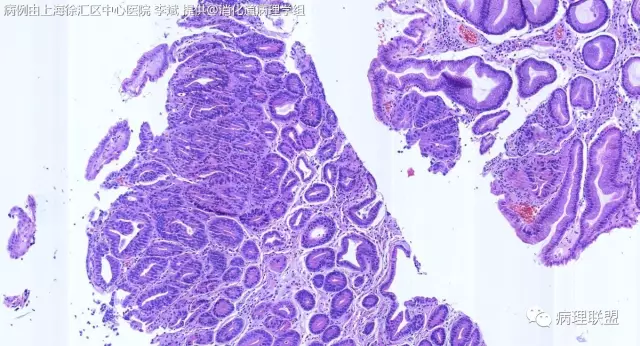

F-56 胃窦粘膜活检(低级别 vs 高级别)

女,56岁,胃窦粘膜活检(病例由上海徐汇区中心医院 李斌 提供,致谢!)

@李斌,高级别,腺体结构乱复杂,核异型性大,极向乱

@左淑英 子宫内膜受激素周期影响,腺体结构和上皮变化比较大,消化道受损伤、炎症等影响比较大,同样要看结构、看细胞,但标准确实不大一样。虽然具体病例需要具体分析,但我感觉在胃肠道,对于判断时感觉模棱两可的病例,表面成熟现象是区分反应性增生和低级别异型时可重复性相对比较好的指标;核极向是区分高低级别异型增生时可重复性相对比较好的指标。供参考